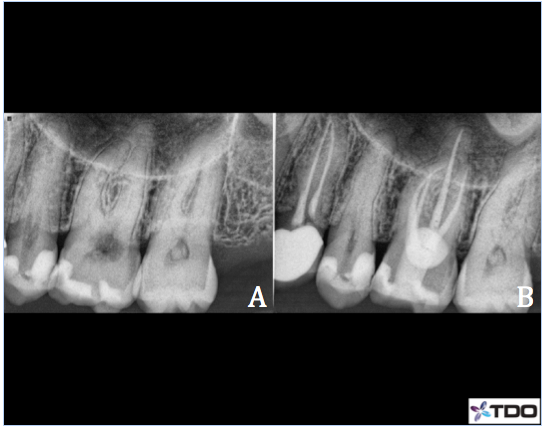

Case 4– #14 ECIR Class III with external surgical repair

48 y/o female presented complaining of a food trap on the palatal surface of #14. She was not experiencing any discomfort. Clinical exam revealed a circular ECIR lesion of about 5mm in diameter on the L surface of #14, extending 1mm subgingivally. The tooth tested WNL to cold was the pulp was vital. Radiographic exam revealed the lesion was superimposed over the pulp chamber and mostly within the cervical 1/3rd of the clinical crown. Apical tissues were WNL and there was no evidence of periapical pathology. Because the lesion is mostly supragingival secondary decay was noted and excavation resulted in a pulpal exposure.

Endodontic treatment was completed. The coronal 3mm of the P canal was filled with Geristore in preparation for the ECIR repair. Palatal tissue was reflected to gain full access to the defect. All decay and resorptive tissue was removed mechanically and I soaked the prep with 90% TCA. Geristore was placed as a restoration and the flap was re-approximated and sutured into place. The patient was referred to her general dentist for the crown. Recall not yet available.